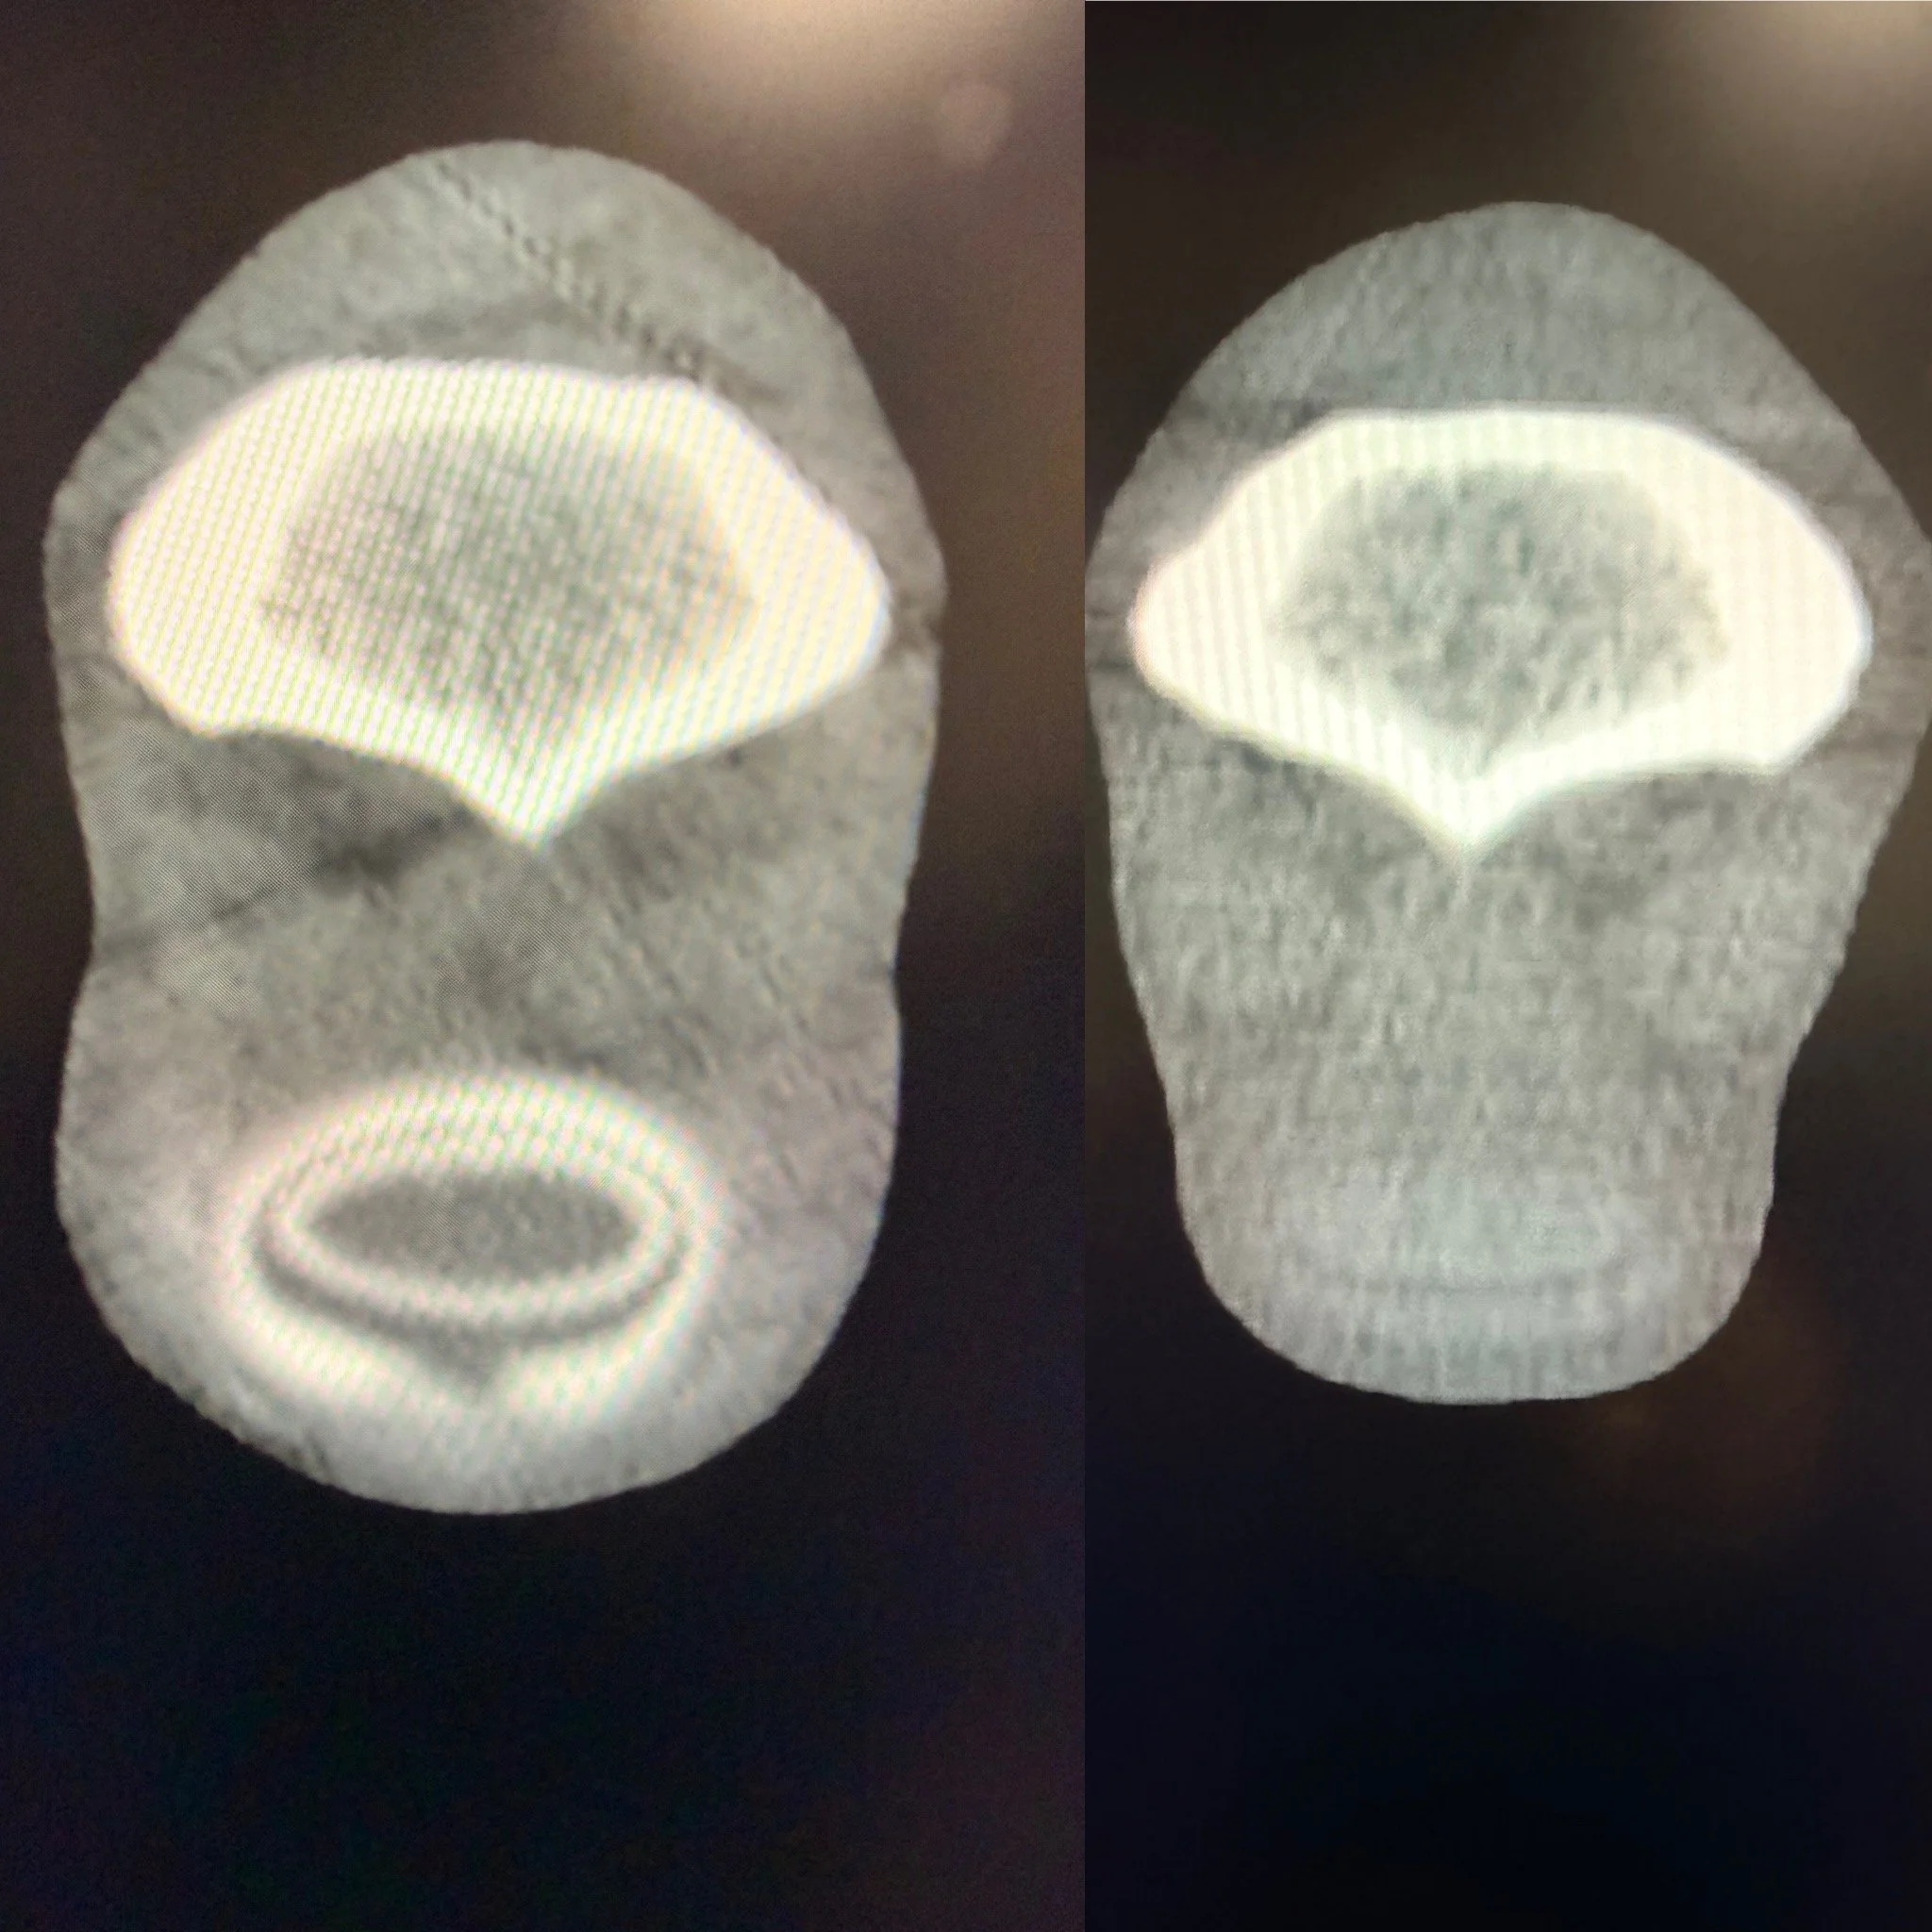

Cross-sectional medical scan image of a human spine viewed from below